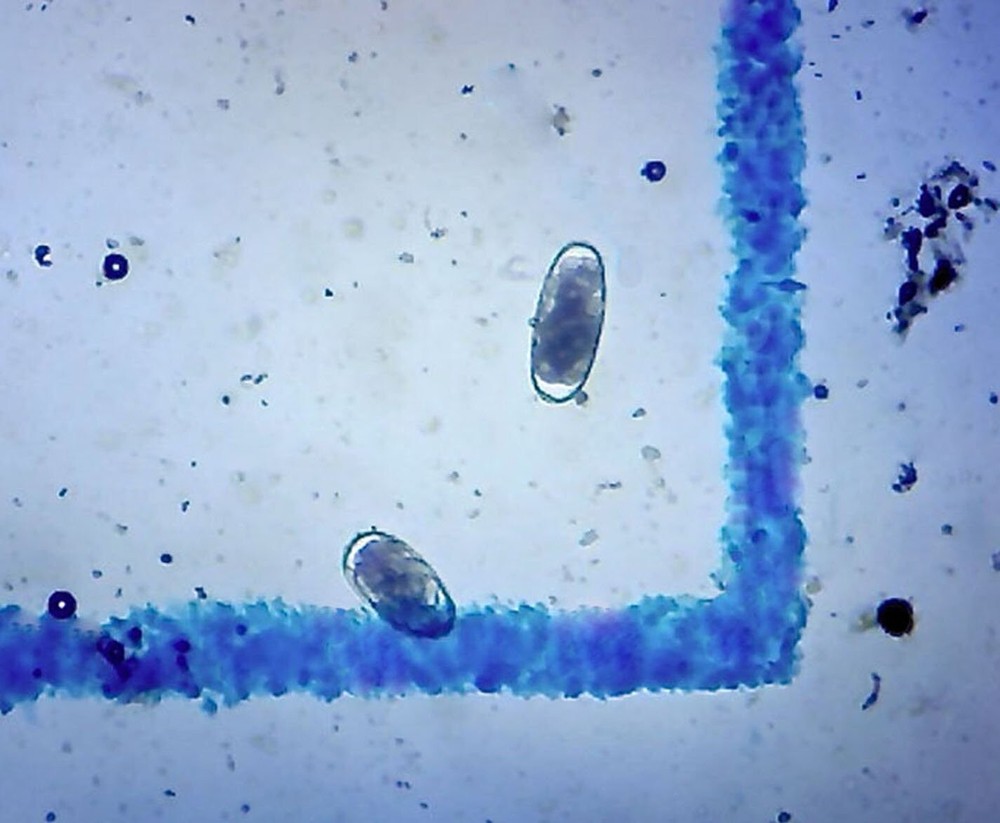

Check the listing for details. Fecal Egg Count Supply - McMaster Method, by . Fecal/Worm Egg Count for Paras.... Condition: New. Listed at 118.99 USD. For use by Labs, Parasitologists, Veterinarians and anyone conducting FEC (Fecal Egg Count) Tests. Fecal/Worm Egg Count for Parasites for Veterinary Use. EPG kit, FEC and FECRT Reference Guide Included.